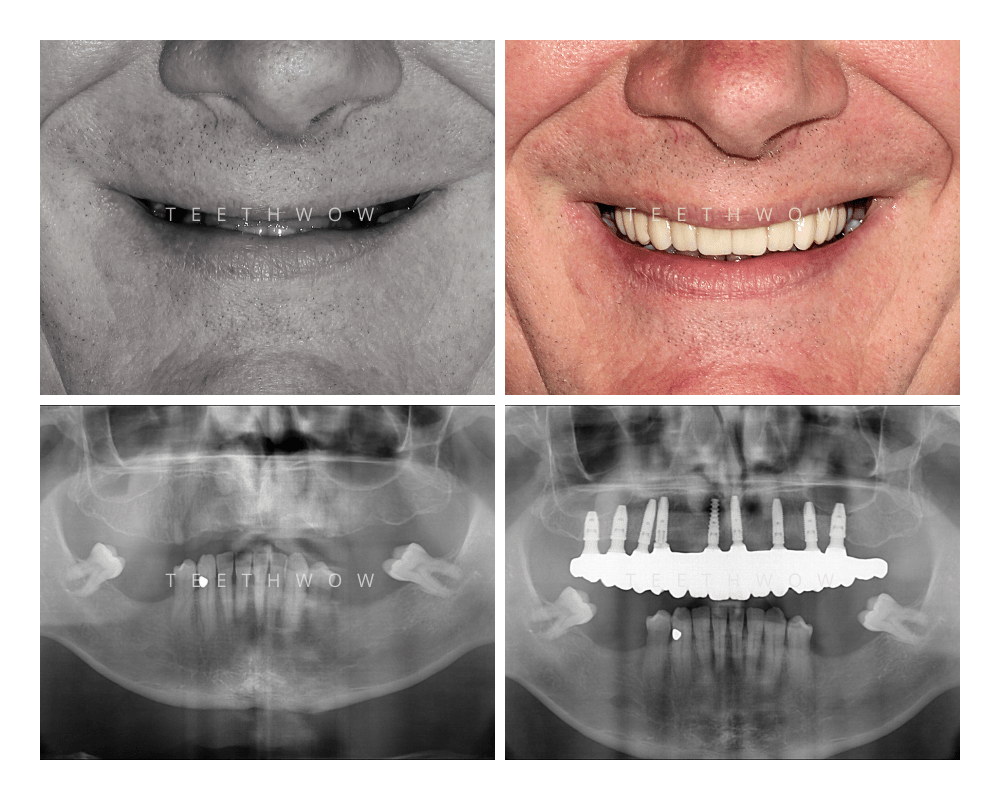

OUR RESULTS

Before and After Cases